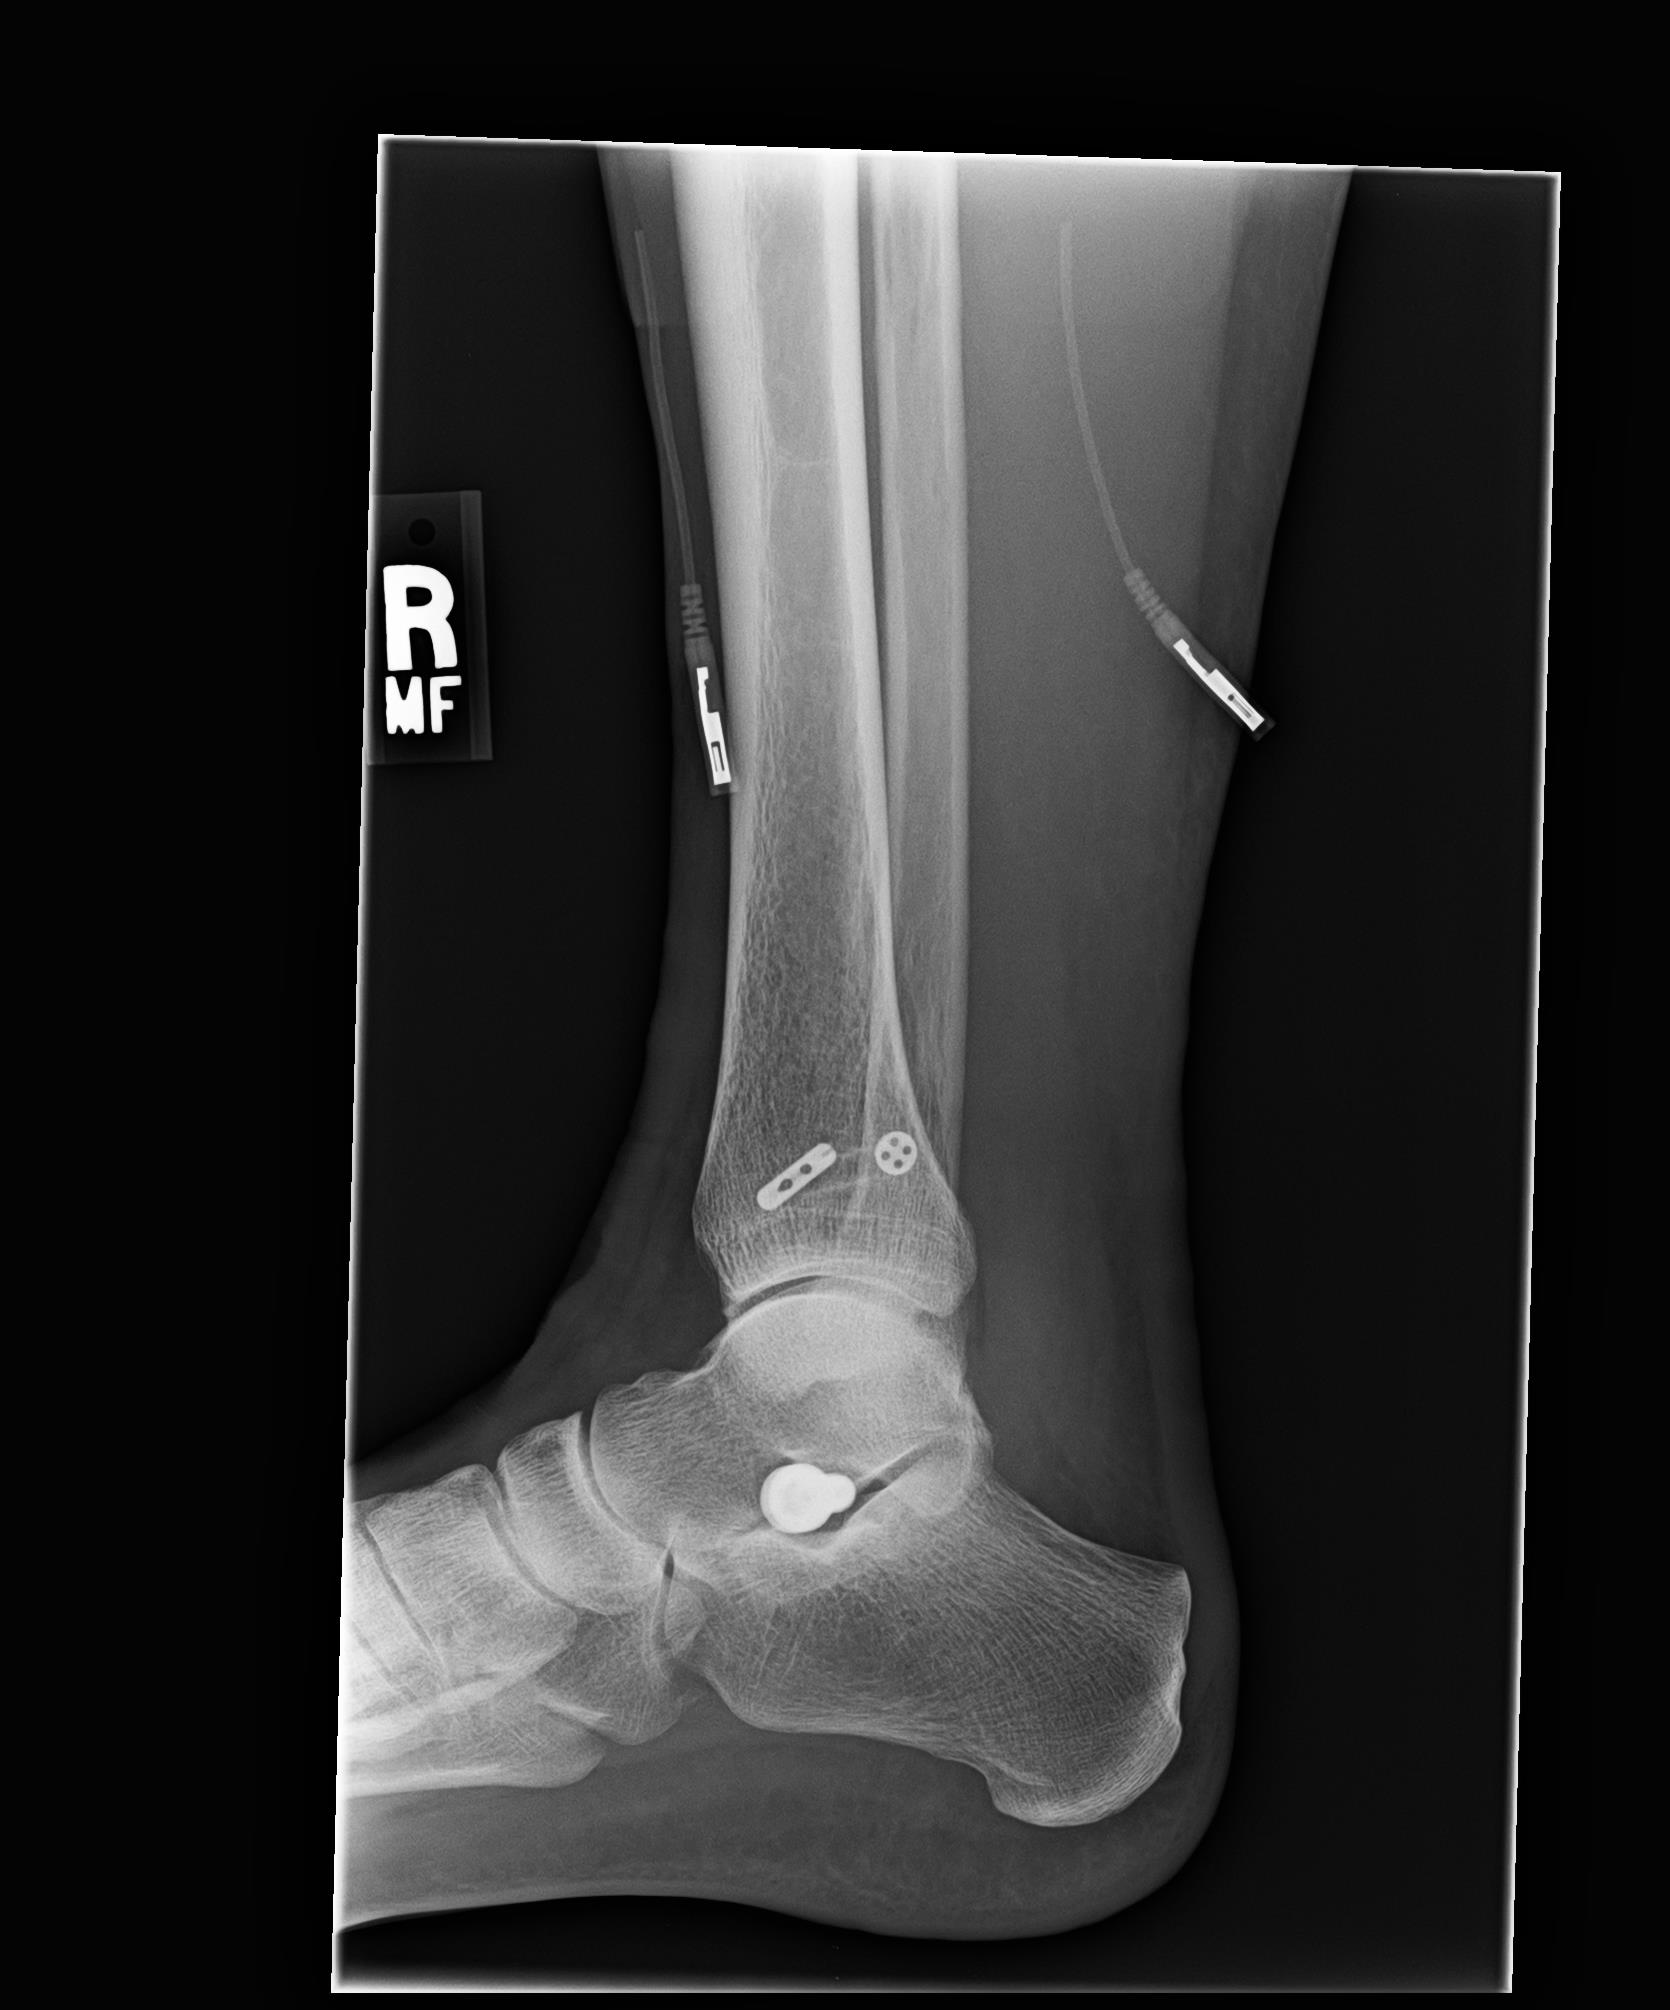

Post surgical X-rays are shown farther down in this blog. For those readers that want the surgical procedure details, please click each link for the PDF pages of the surgical report:

2. Dr. Main and I had discussed my right ankle joint still having some slight pronation and pain around the distal tib-fib. During surgery after doing the proximal fixations and tightening of the proximal syndesmosis, he checked the distal syndesmosis and it still showed some slight instability. He therefore went ahead and placed another Arthrex TightRope Fixation into the distal tib-fib of the ankle. All the fixations can be seen in the X-rays below in this blog.

Monday, 3-31-14— First Follow up appointment at 4 days since surgery. Post surgical x-rays taken of my right lower leg and ankle at Dr. Main’s office (click on photos to enlarge):